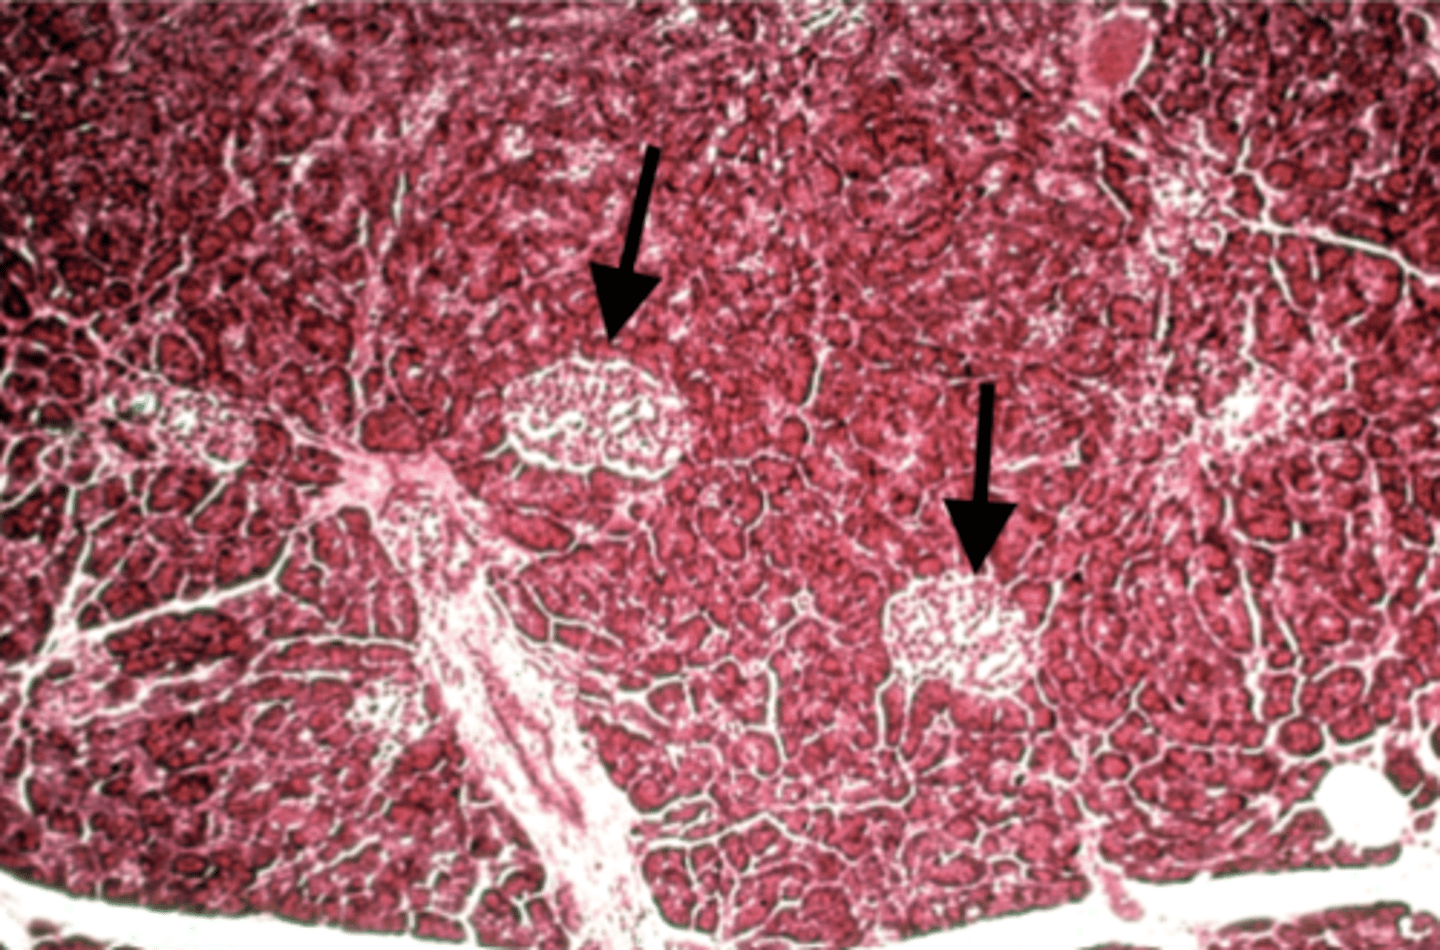

Pancreas

what is this?

Islets of Langerhans

what is this pointing to?

pancreas

what organ is islet of langerhans on